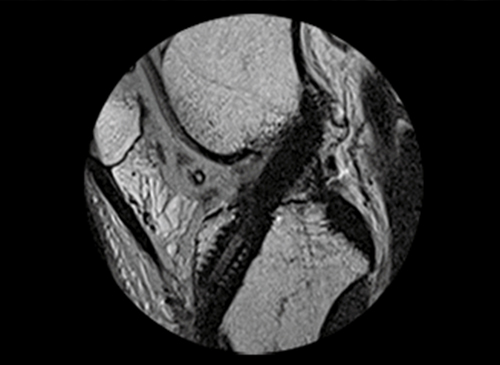

인대 재건술은 관절의 인대가 손상되었거나 파열되었을 경우 시행하는 수술법입니다.

전방, 후방 십자인대, 내-외측 측부인대 등 무릎 관절이 외부 충격이나 손상으로 제 기능을 상실할 경우 시행하는데 새로운 인대를 이식하여 원래의 기능을 되찾아주는 수술 방법입니다. 인대 재건술은 인대 파열 이후 생기는 인대 강도의 약화나 길이 변화에 대해 가장 확실하게 본래의 기능을 회복시켜주는 수술입니다.

십자인대의 경우 관절 내시경을 이용하여 최소 절개방법으로

시행하여 수술 부위가 작고 회복 속도도 빠릅니다. -